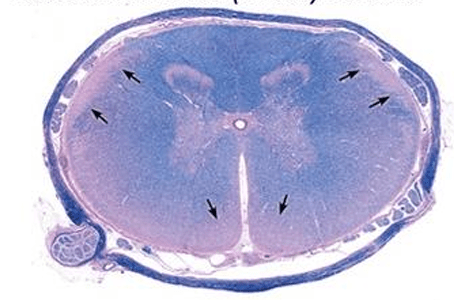

Spinal Cord Anatomy

The part of the spinal cord that primarily contains ASCENDING tracts

What is the dorsal funiculus?